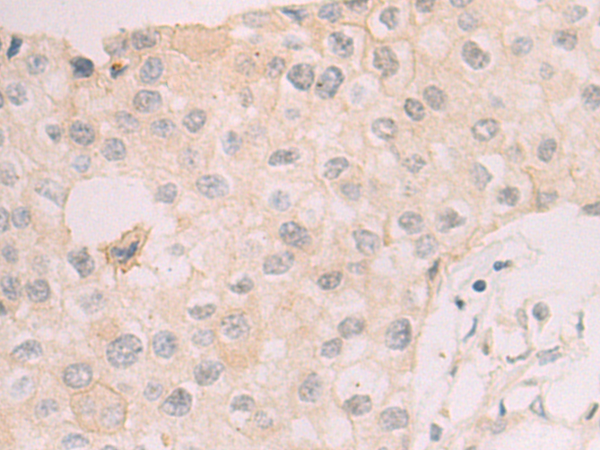

分类: 科研抗体货号: P08108别名:应用: WB,IHC反应种属: Human, Mouse, Rat